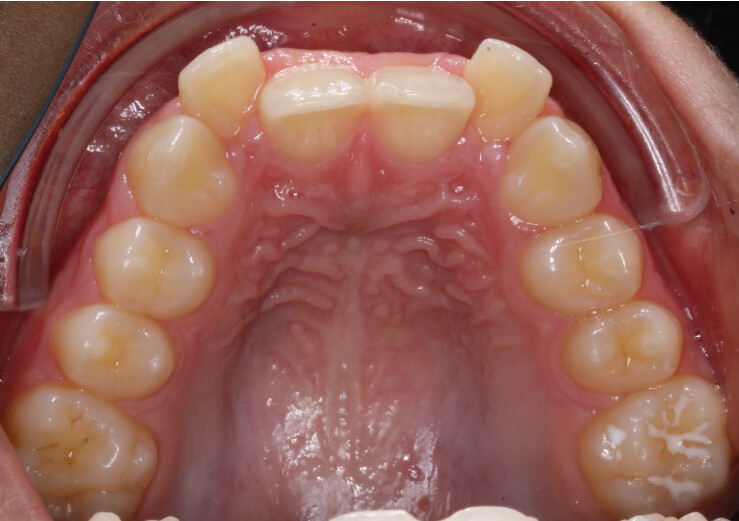

Um paciente do sexo masculino, com 13 anos de idade, apresentou-se com uma mordida profunda, caracterizada pela cobertura quase completa dos incisivos mandibulares. A avaliação clínica revelou apinhamento em ambas as arcadas, rotações dentárias e proclinação dos incisivos laterais superiores, contribuindo para as preocupações estéticas do paciente. O perfil facial era retrusivo, consistente com retrognatismo mandibular, e não foram detectadas anomalias periodontais significativas.

O paciente apresentava uma relação esquelética de Classe II com molares e caninos bilaterais em Classe II e um padrão dentário de Classe II divisão 2. A mordida profunda estava associada a um apinhamento anteroinferior e a uma curva de Spee acentuada. A análise facial revelou boa simetria, um terço facial inferior ligeiramente aumentado e um perfil convexo caracterizado por retrusão mandibular e do mento. A competência labial estava ligeiramente reduzida, com diminuição do ângulo nasolabial e leve tensão do músculo mentoniano, fatores que comprometiam a harmonia facial global.

- Expansão da arcada para resolver o apinhamento e melhorar a coordenação transversal;

- Intrusão programada dos incisivos centrais superiores para reduzir a exposição gengival e corrigir o sorriso gengival;